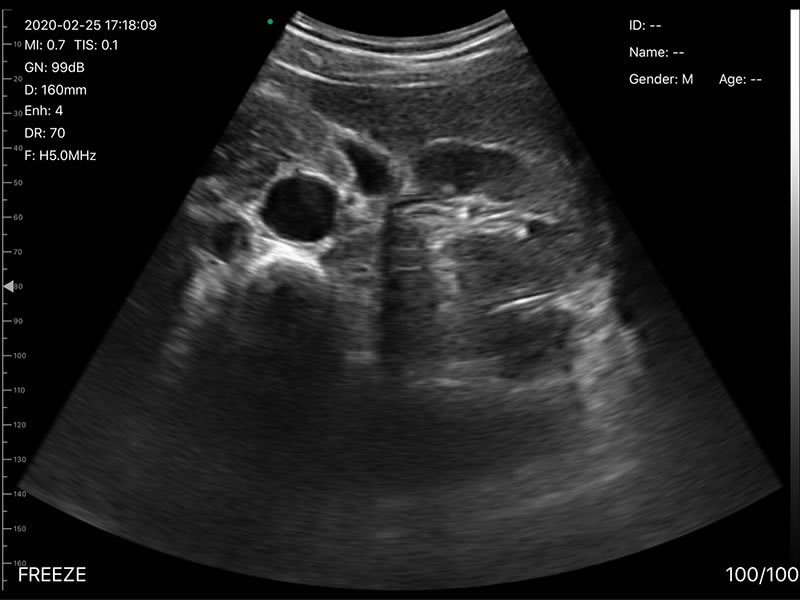

• 探头频率:凸阵/相控阵3.2/5.0MHz,线阵7.5/10MHz,心脏模式3.2-5MHZ

• 扫描深度:凸阵90/160/220/305mm,相控阵90/120/140/160,线阵20/40/60/80mm,可调

• 扫描角度和宽度:凸阵60°,相控阵80°,线阵宽度40mm